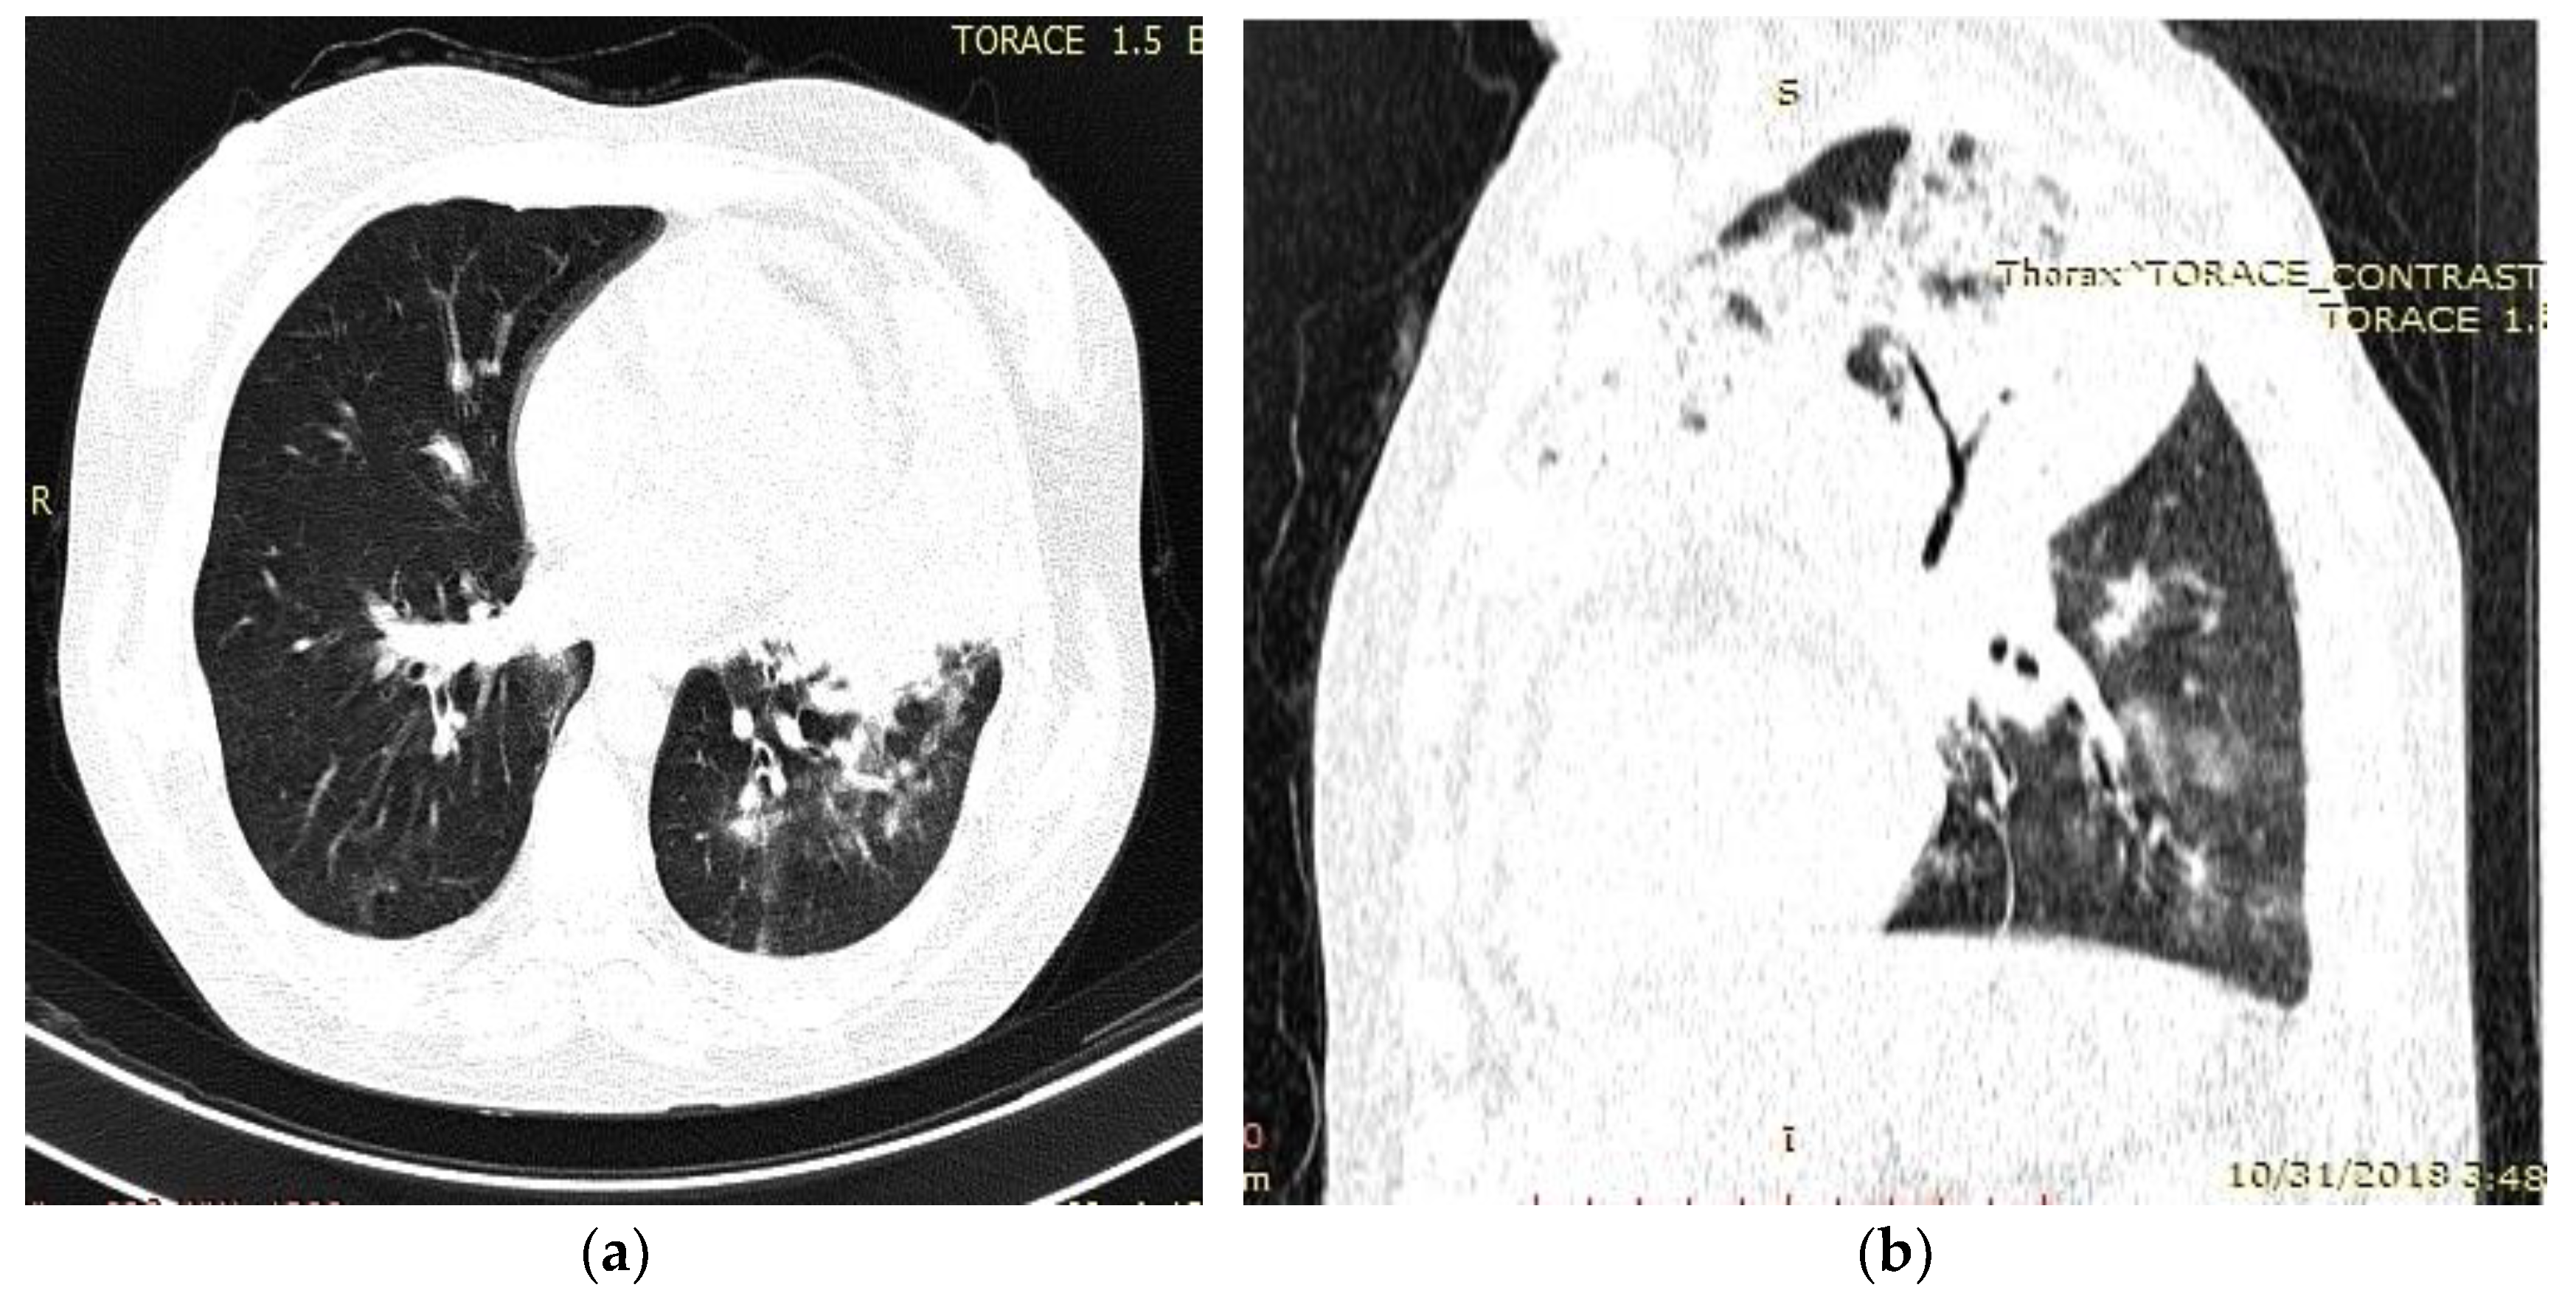

2. Detailed Case Description

- Radiological evidence of chronic pulmonary lesion;

- Mycological demonstration of Aspergillus fumigates hyphae by microscopy from spu-tum, microscopy and culture from bronchial aspirate, and histopathological evi-dence of the presence of Aspergillus fumigates hyphae with dichotomous branching in the spinal cord biopsy;